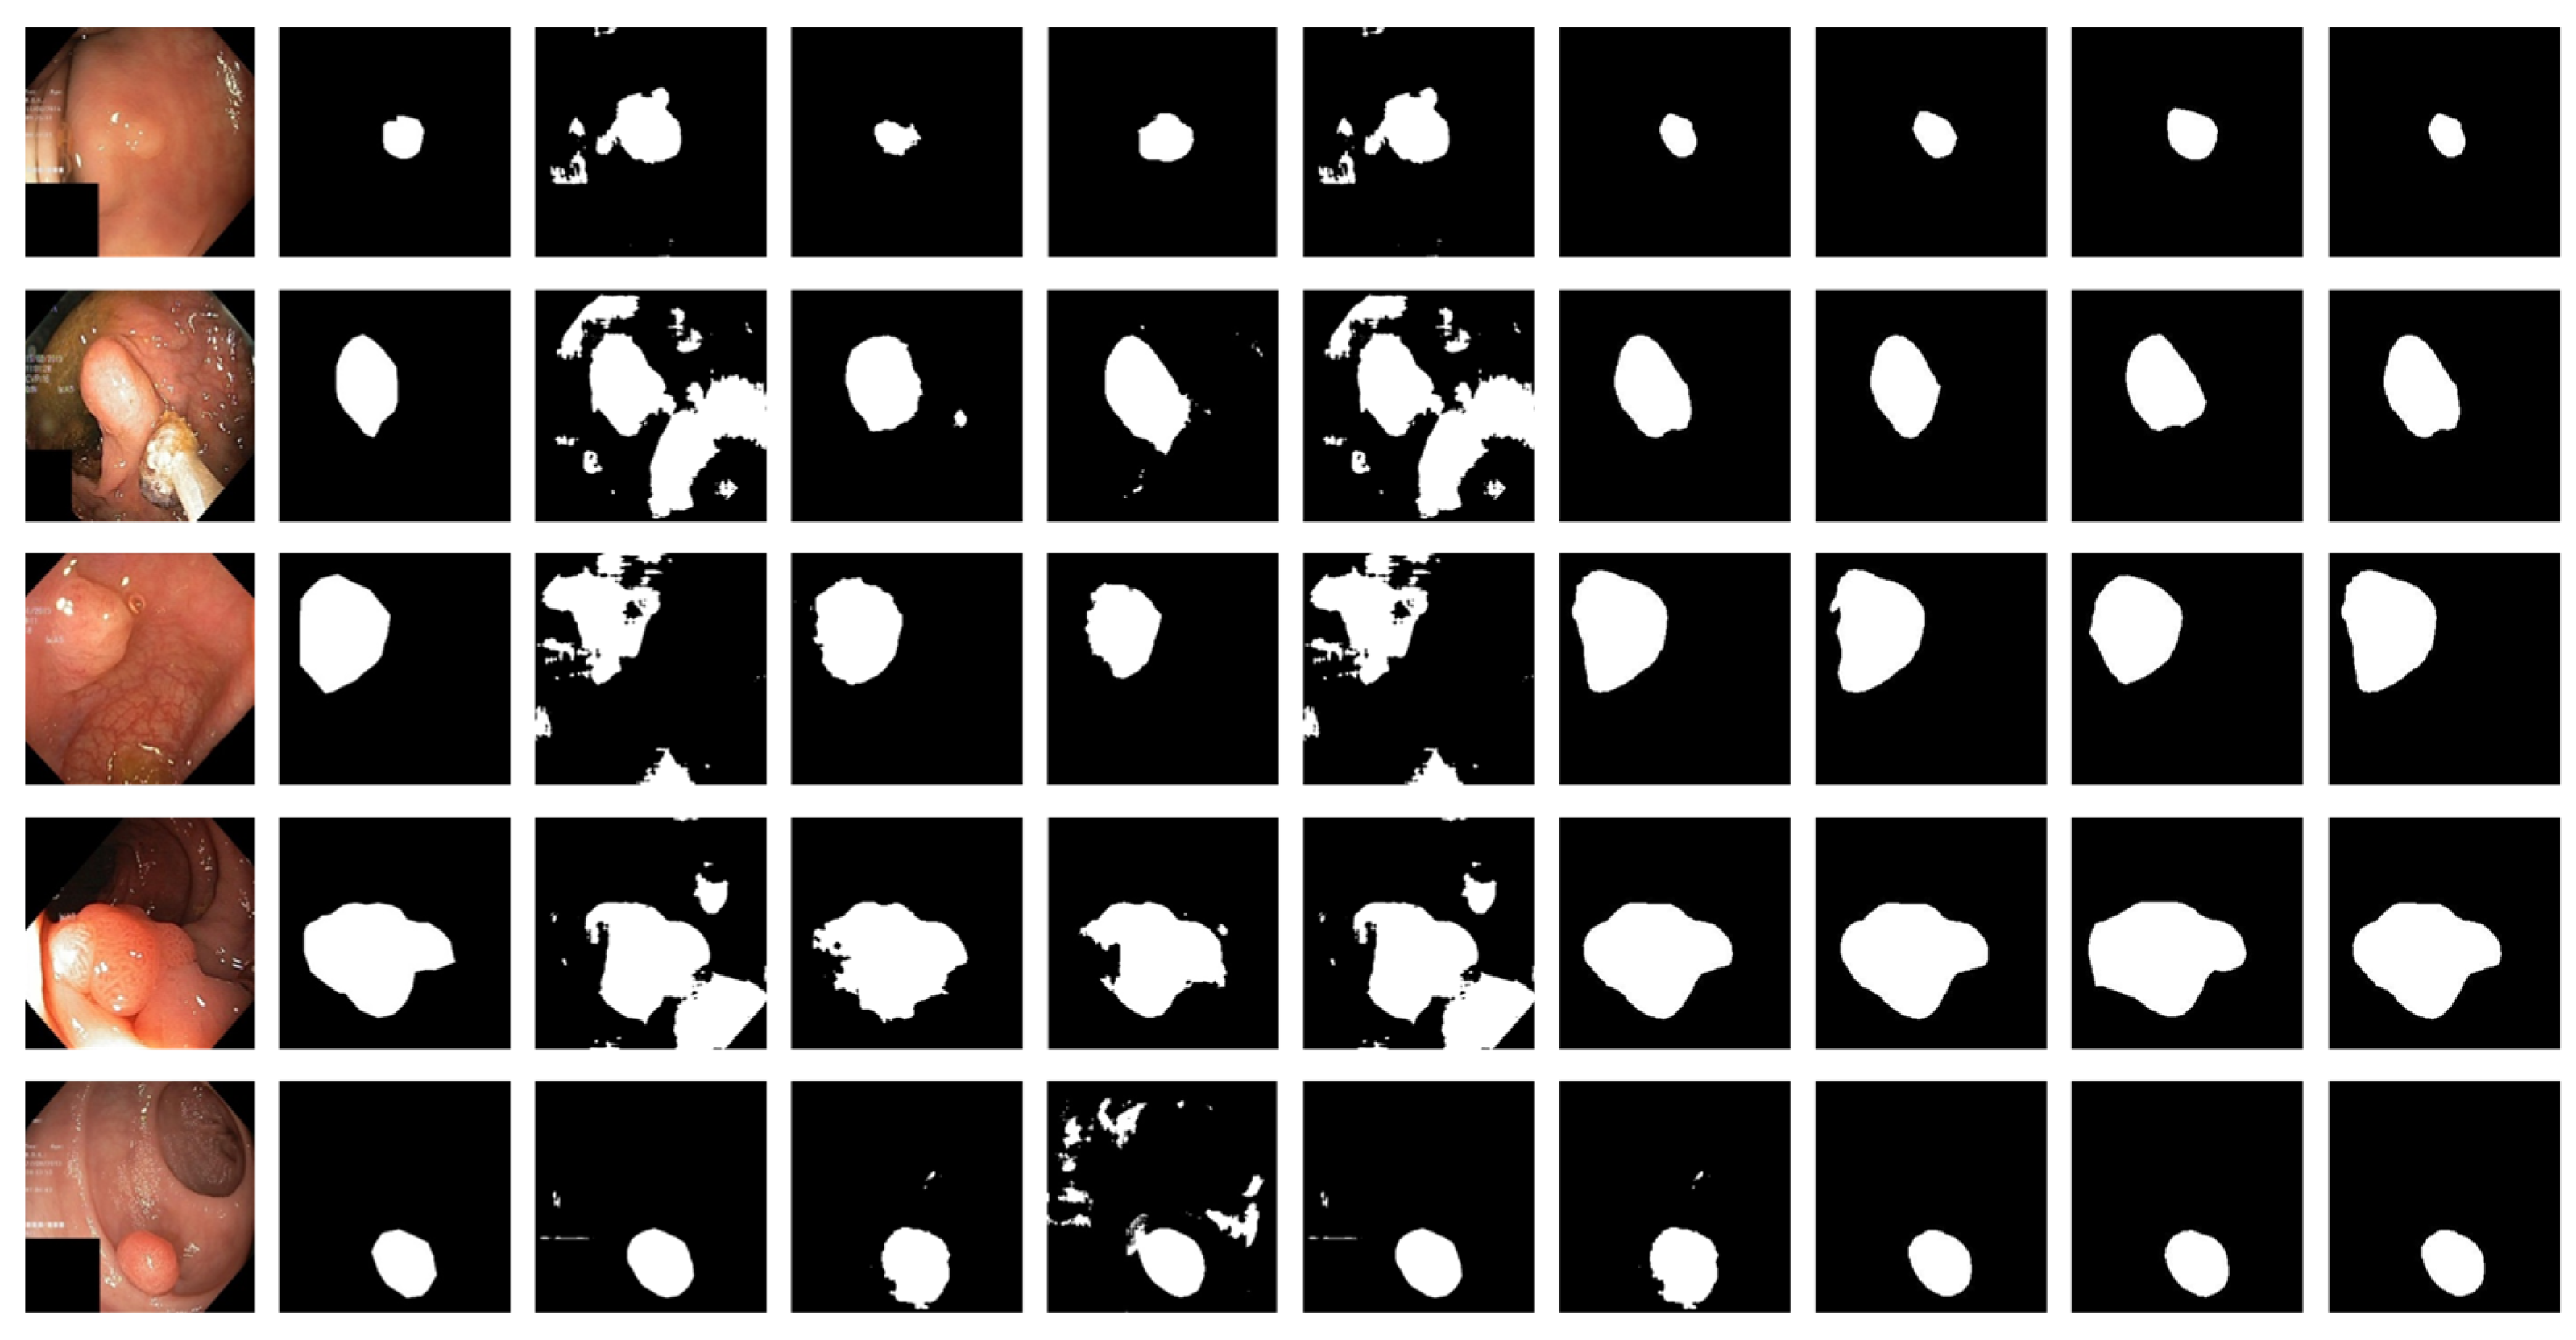

Figure 6 shows the qualitative results for all models. Figure 7 shows the highlighting of TN, TP, FP, and FN by assigning different colors to the pixels of each category, where TN is black, TP is white, FN is red, and FP is blue. In Table 3 and Figure 6, the advantages of the PRAPNet over the baseline architectures are shown. The quantitative and qualitative results all show that the PRAPNet model trained on the Kvasir-SEG dataset showed satisfying results and transcended the other seven models in terms of the dice coefficient, mIoU, and precision. Therefore, in the task of medical image segmentation, the PRAPNet architecture has obvious advantages over the other segmentation methods.

The PRAPNet architecture proposed in this paper achieved satisfactory results from the Kvasir-SEG dataset. From Figure 6, it could be concluded that, from the Kvasir-SEG dataset, the segmentation maps generated by the PRAPNet outperformed the other architectures in capturing the shape information, demonstrating that the segmentation masks generated in the PRAPNet showed more precise information in the target area than the existing models. The full convolutional network has room for improvement in capturing the polyp location and edge details.

Figure 6. Comparison of qualitative results from the Kvasir-SEG dataset. From left to right are the image, the mask, and the segmentation results of unet, U-Net++, ResUNet++, praNet, SFFormer-L, TransFuse-L, CaraNet, and PRAPNet.